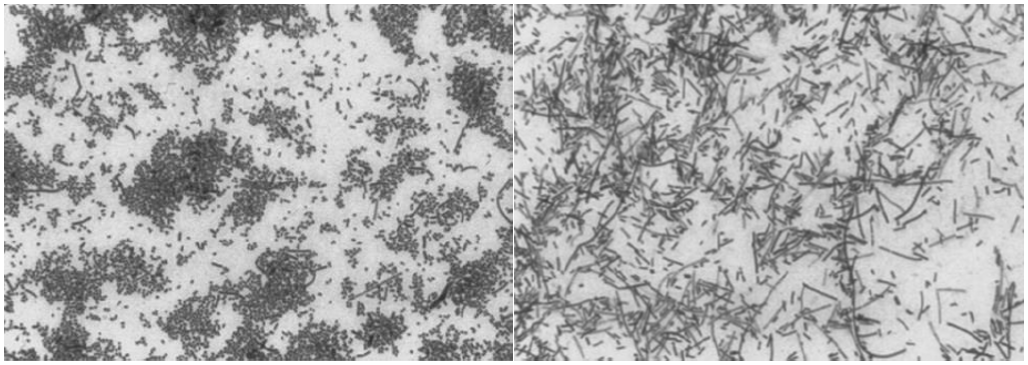

坏死梭杆菌(F.necrophorum)是一种丝状、无孢子的厌氧革兰氏阴性杆菌,与其他梭杆菌相比,它具有独特的多形性形态,可呈丝状、短棒状、球状。

图片

图片来源:Clin Infect Dis, 2000, 31(2):524-532.